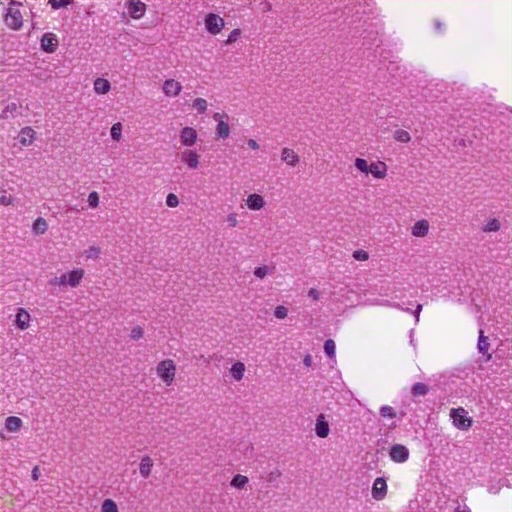

The renal tissue image displays clear cell renal cell carcinoma (RCC) characterized by cells with clear cytoplasm, round to oval nuclei, prominent nucleoli, and a rich vascular network. The clear cell cytoplasm dissolved in the cytoplasm due to dissolved and eosinophilic and pleomorphism. The tissue architecture is distorted, lacking normal renal structures, suggesting the malignancy, the most common subtype of renal carcinoma. L regions show clear cytoplasm, dissolved due to lipids/carbohydrate accumulation or carbohydrates, and stromal necrosis, significant vascular invasion. These features indicate a renal neuroendocrine subtype of lateral carcinoma, specifically clear cell RCC. Nuclei are visible post-staining, with abundant cytoplasm due to dissolved lipids and unremarkable nuclei. No organized glomeruli or tubules is visible, further support the diagnosis, characterized as renal cell carcinoma or a tubular-inian neoplasm.

The renal biopsy reveals tubular intraluminal foamy macrophages with vacuolated cytoplasm, indicative of pathology. Accompanying interstitial tissue shows moderate inflammatory in. Tubular atrophy and dilation suggests potential damage. No necrosis. Absence of clear glomeruli further suggest infiltration. These findings point to xantholytic interstitial macrophages or lipid macrophages, potentially associated with lipiduriarelated material and lipid pathology. The findings suggest a renal pathology linked to proteinuria or disease. The glomerular glomerulus suggests an ongoing inflammatory process, likely related to respiratory kidney disorder. Confirmation requires further testing for specific renal pathology. Key pathology include tubular atrophy, interstitial inflammation, and edema in the sinusoids, evidenced by cellularity at the magnification and accompanied by chronic inflammatory response. disease. Tubular lumina are swoled, while the lining are reduced and vacuolization.

The image likely represents a liver biopsy, showing dense connective tissue, numerous hepatocytes with varying nuclear staining, and potential lipid droplets or vacuoles. Hepatocytes like large nuclei with central nucleoli and a trabecular architecture suggest possible pathology. No fibrosis or cirrhosis are evident. Likely liver tissue, possibly fibrosis, inflammation, or neoplastic changes.atoxylin and eosin staining highlights mixed cell nuclei and possible possible Kupffer or or inflammatory cells. No clear clear demarcation of liver pathology or significant inflammation is visible. The presence of congestedusoid hints at fibrosis or cirrhosis; Likely conditions include reactive changes, hyperplasia, steatosis, or heastatic carcinoma. Further data is needed for a definitive diagnosis. The tissue shows a nuclei- oriented structure and the absence of any portal tracts like bile ducts and portal tracts, indicating normal liver histology.